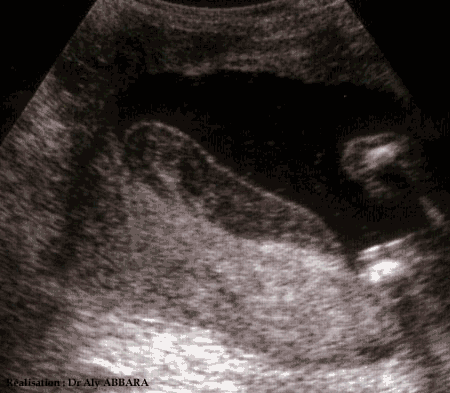

Hématome de la face fœtale du placenta à 18 semaines d'aménorrhée